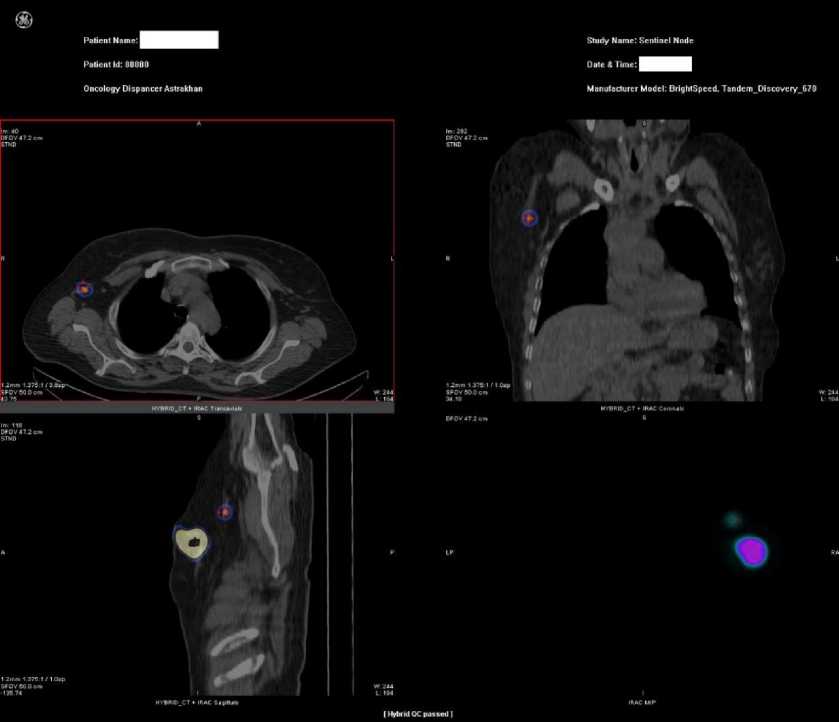

Анализ сцинтиграмм проводили на предмет наличия фокусов накопления 99mTc-Нанотоп в месте его инъекции и очагам гиперфиксации, которые соответствовали сторожевым лимфатиче- ским узлам (рис. 2).

Рис. 2. Однофотонная эмиссионная компьютерная томография сторожевого лимфатического узла пациентки М. с гиперфиксацией 99mTc-Нанотопа в аксиллярном лимфоузле.

Спроецированная на кожу локализация сторожевого узла отмечалась на ней маркером. Во время операции с помощью портативного гамма-сканера Rad Pointer Gamma идентифицировали лимфатические узлы, являющиеся сторожевыми. Интенсивность высокой фиксации РФП характеризовалась более сильным звуковым сигналом и большим числом импульсов, исчисляемых в минуту.